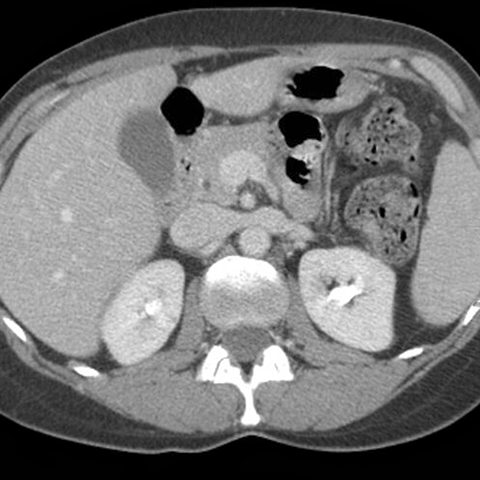

Abdominal Vessels, axial CT [3 of 6]